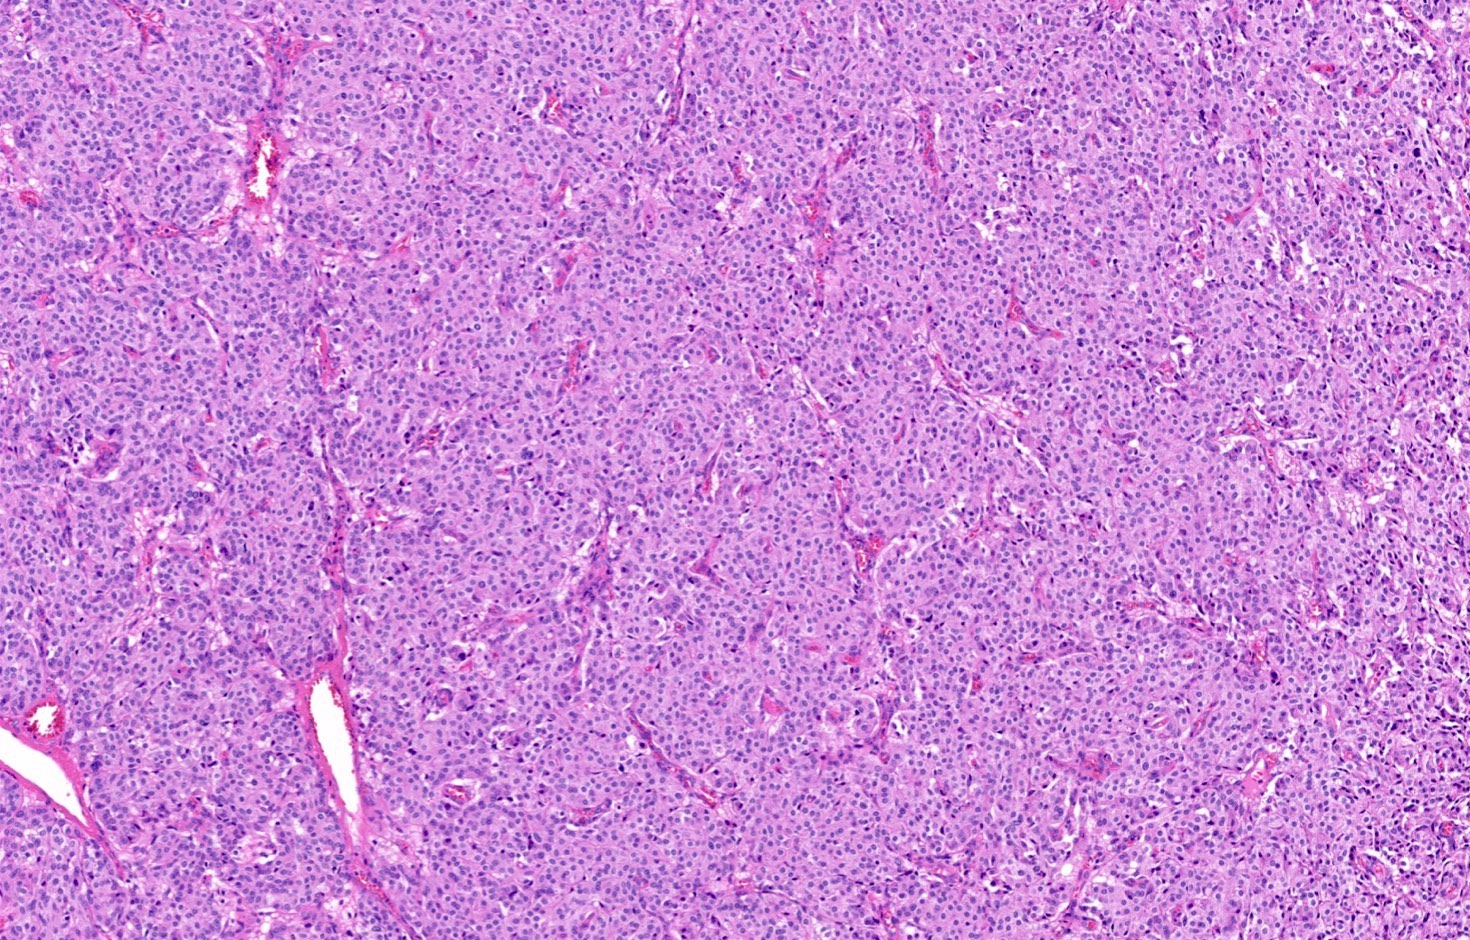

Microscopic (histologic) description

- Diagnostic criteria

- Neuroendocrine tumor with size ≥ 5 mm with < 2 mitoses/2 mm2 and absence of necrosis

- Neuroendocrine growth pattern (organoid, trabecular, rosette formation, nested) or pseudoglandular, follicular and papillary growth

- Tumor cells are uniform with a polygonal shape, round to oval nuclei with salt and pepper chromatin as well as inconspicuous nucleoli and moderate to abundant eosinophilic cytoplasm

- Spindle cells and clear cell features can be seen

- Stroma is fine and highly vascularized; hyalinization, cartilage or bone formation are possible

- Reference: Curr Oncol 2018;25:S86

Microscopic (histologic) images

Contributed by Philippe Joubert, M.D., Ph.D., Jijgee Munkhdelger, M.D., Ph.D. and Andrey Bychkov, M.D., Ph.D.

A 55 year old woman had a lower left lobectomy showing a well circumscribed flesh colored tumor. Histologic details are shown in the image above. Regarding this entity, which of the following statements is true?

Practice answer #1

A. CDX2 is usually negative in the lung and is useful to differentiate from a metastasis of an intestinal origin. The image shows a tumor with a trabecular pattern and pseudorosettes. The stroma is highly vascularized. Tumor cells are monotonous with scant to moderate eosinophilic cytoplasm. Nuclei are round to oval with salt and pepper chromatin and inconspicuous nucleoli. No mitoses are seen. These features are consistent with a typical carcinoid lung tumor.

Ki67 immunostaining, counter to well differentiated neuroendocrine tumors from the gastrointestinal tract, is not essential to grade the tumor. The difference between typical and atypical tumor relies on mitosis count and the presence of necrosis. However, Ki67 is useful to differentiate from high grade neuroendocrine tumors (small cell and large cell neuroendocrine carcinomas) on small biopsies with artifacts. TTF1 is positive in only half of cases with a higher frequency in peripheral tumors. Rb expression is preserved in typical carcinoid lung tumors, unlike in small cell tumors.